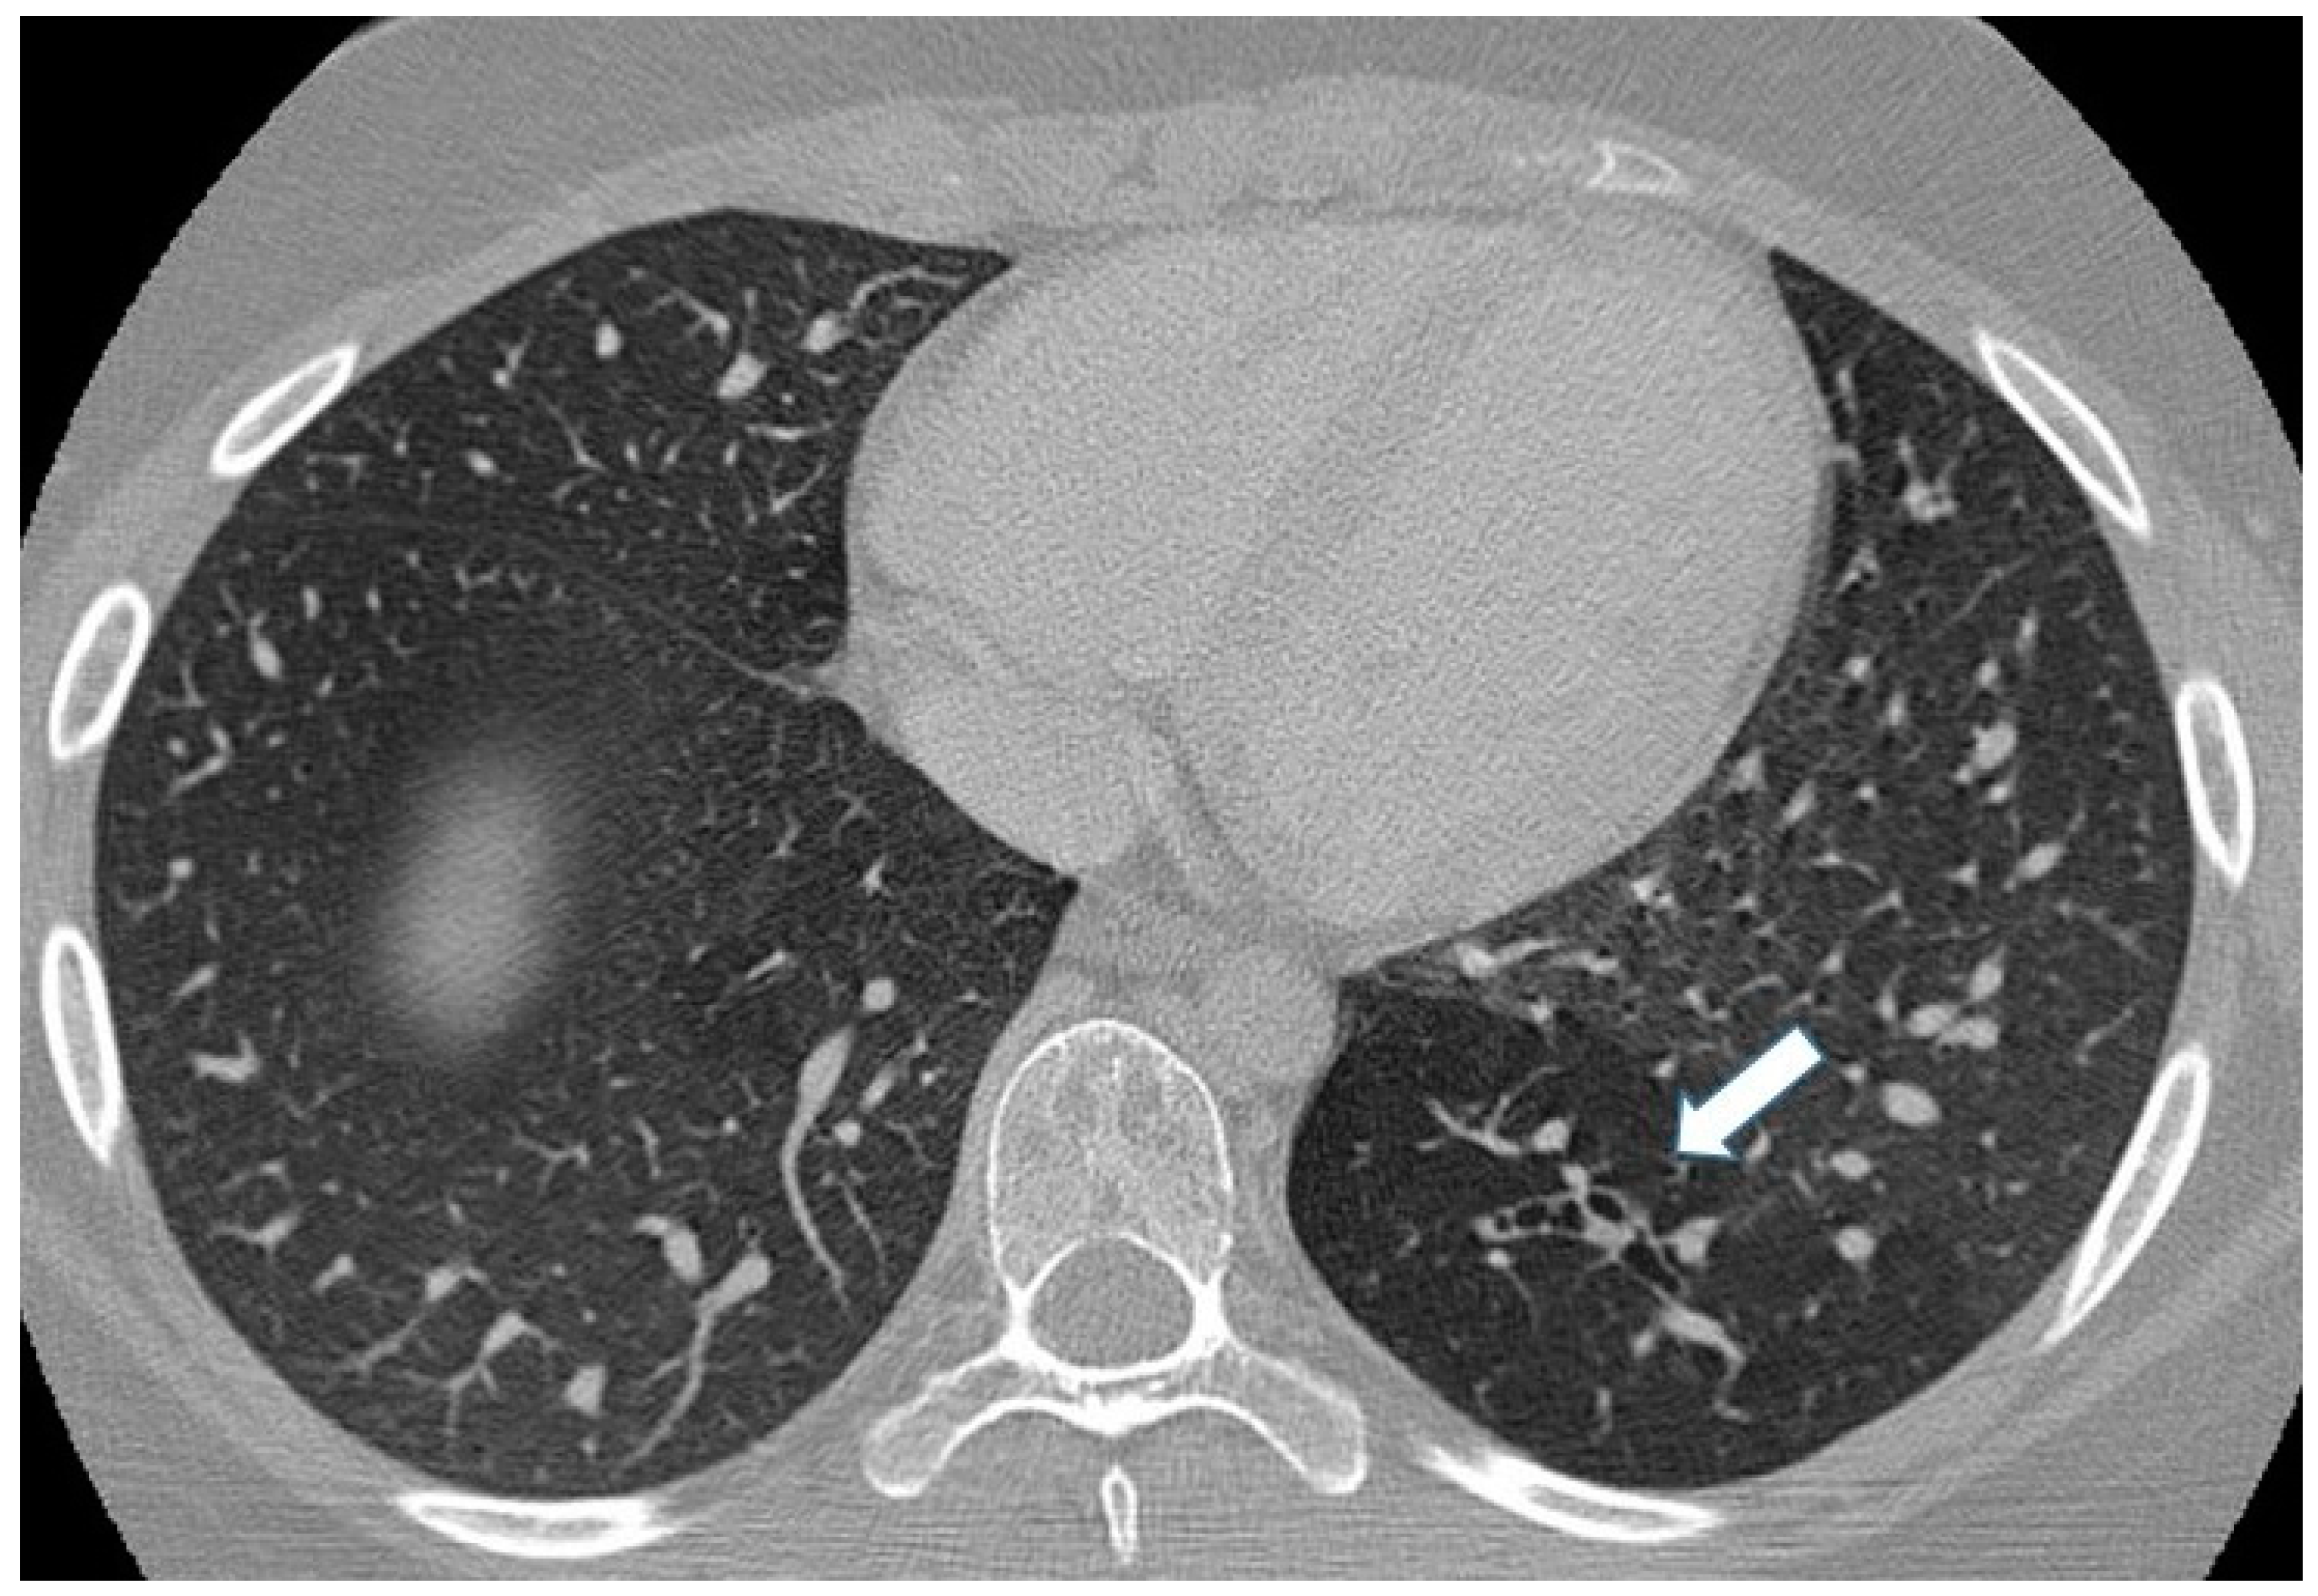

Figure 10.

Incidental finding of bronchial atresia during a CT scan in a 15-year-old girl with lymphoma. In the left lower lobe, a tubular-shaped opacity (mucoid-filled bronchus) is associated with segmental hypoattenuation (arrow).